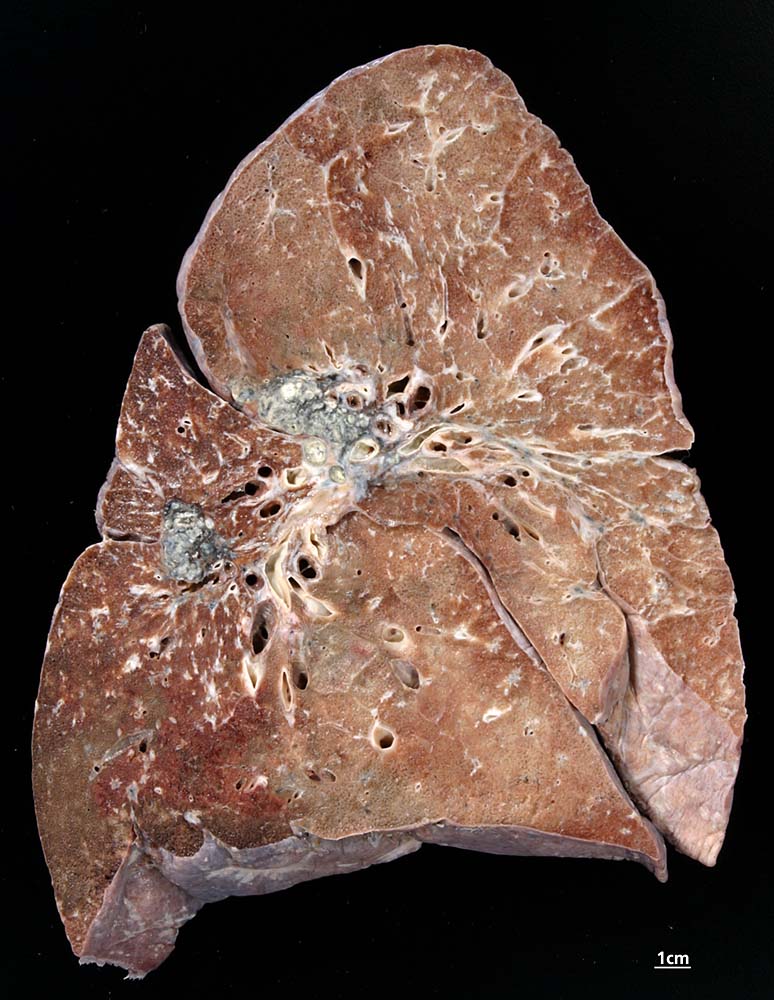

Die Morphologie der Erkrankung ist stadienabhängig. Initial findet sich eine lymphozytenreiche Alveolitis mit wenigen kleinen Granulomen. Die Granulome bestehen aus Aggregaten epitheloider Histiozyten teilweise mit Beteiligung von mehrkernigen Riesenzellen. Im Verlauf entwickeln sich zellreiche Granulome entlang der bronchovaskulären Bündel und der Interalveolarsepten, welche später konfluieren und vernarben. Die Riesenzellen können Asteroidkörperchen (sternförmige Kristalle) oder Schaumannkörperchen (lamelläre Verkalkungen) enthalten. Ein Teil der Patienten entwickelt eine irreversible Lungenfibrose.

• Zahlreiche produktive, nicht nekrotisierende Granulome aus dickleibigen Epitheloidzellen, Riesenzellen vom Langhanstyp und Lymphozyten.

• Ausgeprägte Fibrosierung der Granulome.

• Herdförmige Vernarbung des Lungenparenchyms.

• Bevorzugte Lokalisation der Granulome im Bereich von Bronchiolen und Pulmonalarterienästen. Das sollte der Kliniker dem Pathologen mitteilen:

Makroskopie